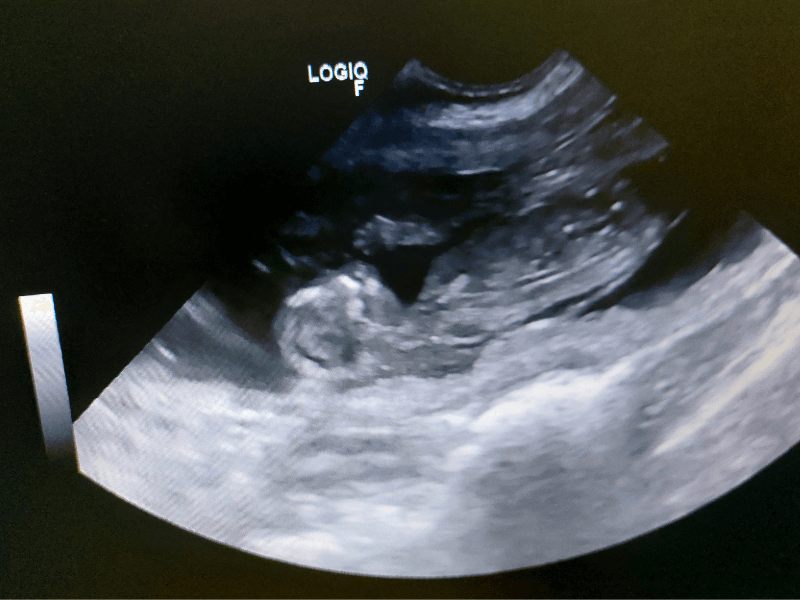

Uta, een 4,5 jarige Border Terriër, komt op de praktijk voor een echo. Haar eigenaar is een groot liefhebber en ervaren fokster van dit leuke ras. Om zeker te weten of Uta inderdaad drachtig is, uitwendig is dit nog niet duidelijk zichtbaar, wordt een echo gemaakt.

Middels echografisch onderzoek is het vanaf een dag of 28 na de dekking mogelijk om dracht vast te stellen. Hiervoor wordt het buikje geschoren en Uta in alle rust op een comfortabel kussen gelegd.

Gelukkig was er goed nieuws: bij Uta waren duidelijk meerdere foetussen te zien! Doordat je met echo onderzoek geen totaaloverzicht in beeld krijgt, is het lastig om het aantal pups met zekerheid vast te stellen.